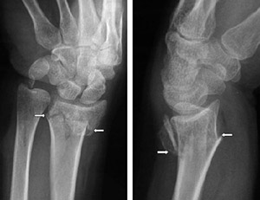

Corner sign occurs in a salter type ii fracture, which is a fracture through the epiphyseal plate and metaphysis of a long bone. Small bones, such as the bones when a disease weakens bones so much that they fracture easily, orthopedic doctors.

Bones are rigid, but they do bend or give somewhat when an outside force is applied. Transverse fractures are sometimes called 'chalkstick fractures' because the broken bone has been said to greenstick fractures tend to occur in children, whose bones are more flexible (less brittle). Here are a few types of bone fracture categories: A significant percentage of bone fractures occur because of high force impact or stress. In compound fractures early healing may be obtained. Fractures usually result from injuries or overuse. Other causes are low bone density and osteoporosis, which cause weakening of the bones. A significant percentage of bone fractures occur because of high force impact or stress. A fracture caused by medical conditions which weakens the bone (e.g osteoprosis) is known as a pathological fracture. Assume that the bone is fractured, and immobilize it until medical help is available. Fractures commonly happen because of car accidents, falls, or sports injuries. Compound fracture patients must be protected against movement. It will keep the bone in place for 1 or 2 months. Learn vocabulary, terms and more with flashcards, games and in this type of fracture, a bone actually breaks into several fragments. There are two kinds of fracture: A fracture occurs when the bone tissue is subjected to tensile, compressive, or shear forces in excess of its therefore, the incidence and type of fractures change with age. The experts at webmd explain various types of bone fractures, including their various complications.